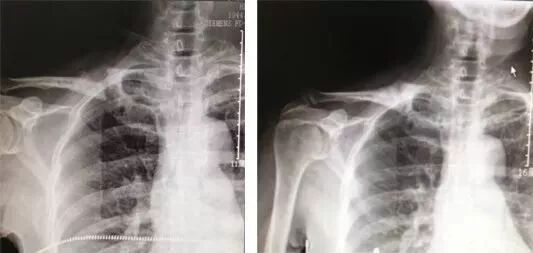

病例一

上肢多發(fā)骨折

患者張某,女,26歲,車禍致右肱骨髁間粉碎性骨折,右橈骨遠端、尺骨莖突骨折,跑了幾家醫(yī)院都建議手術(shù)治療,在當(dāng)?shù)匾患夜莻t(yī)院住院保守治療一周后還是建議進行手術(shù)。

患者因有5個月的身孕,不愿為了手術(shù)放棄胎兒。后經(jīng)人介紹,聽聞?wù)诟魂枏埵瞎莻诩闻d邦爾骨科醫(yī)院,于是前來我院就診,進行手法整復(fù)、固定以及外敷張氏金黃散。

經(jīng)過每周一次換幫,一個半月骨折愈合,三個月后肘關(guān)節(jié)、腕關(guān)節(jié)的外觀及功能完全正常。

手法整復(fù)前后對比圖